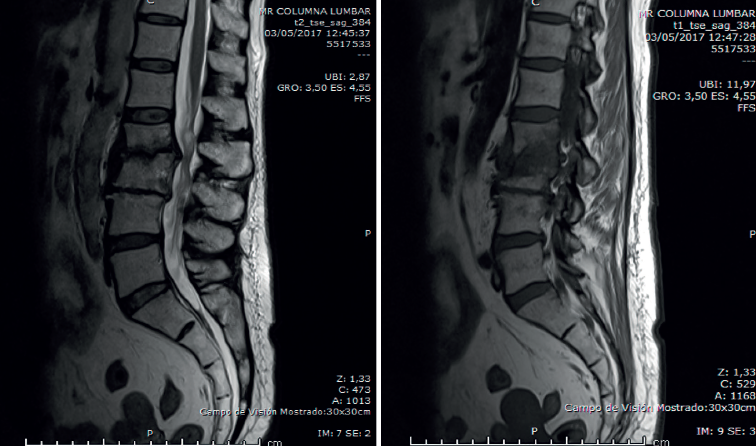

La analítica se había normalizado. En la radiografía lumbar (Figura 3) se veían signos de discopatía grave.

En la RM lumbar (Figura 4) se observaba desaparición de los abscesos preexistentes. Discopatía evolucionada.